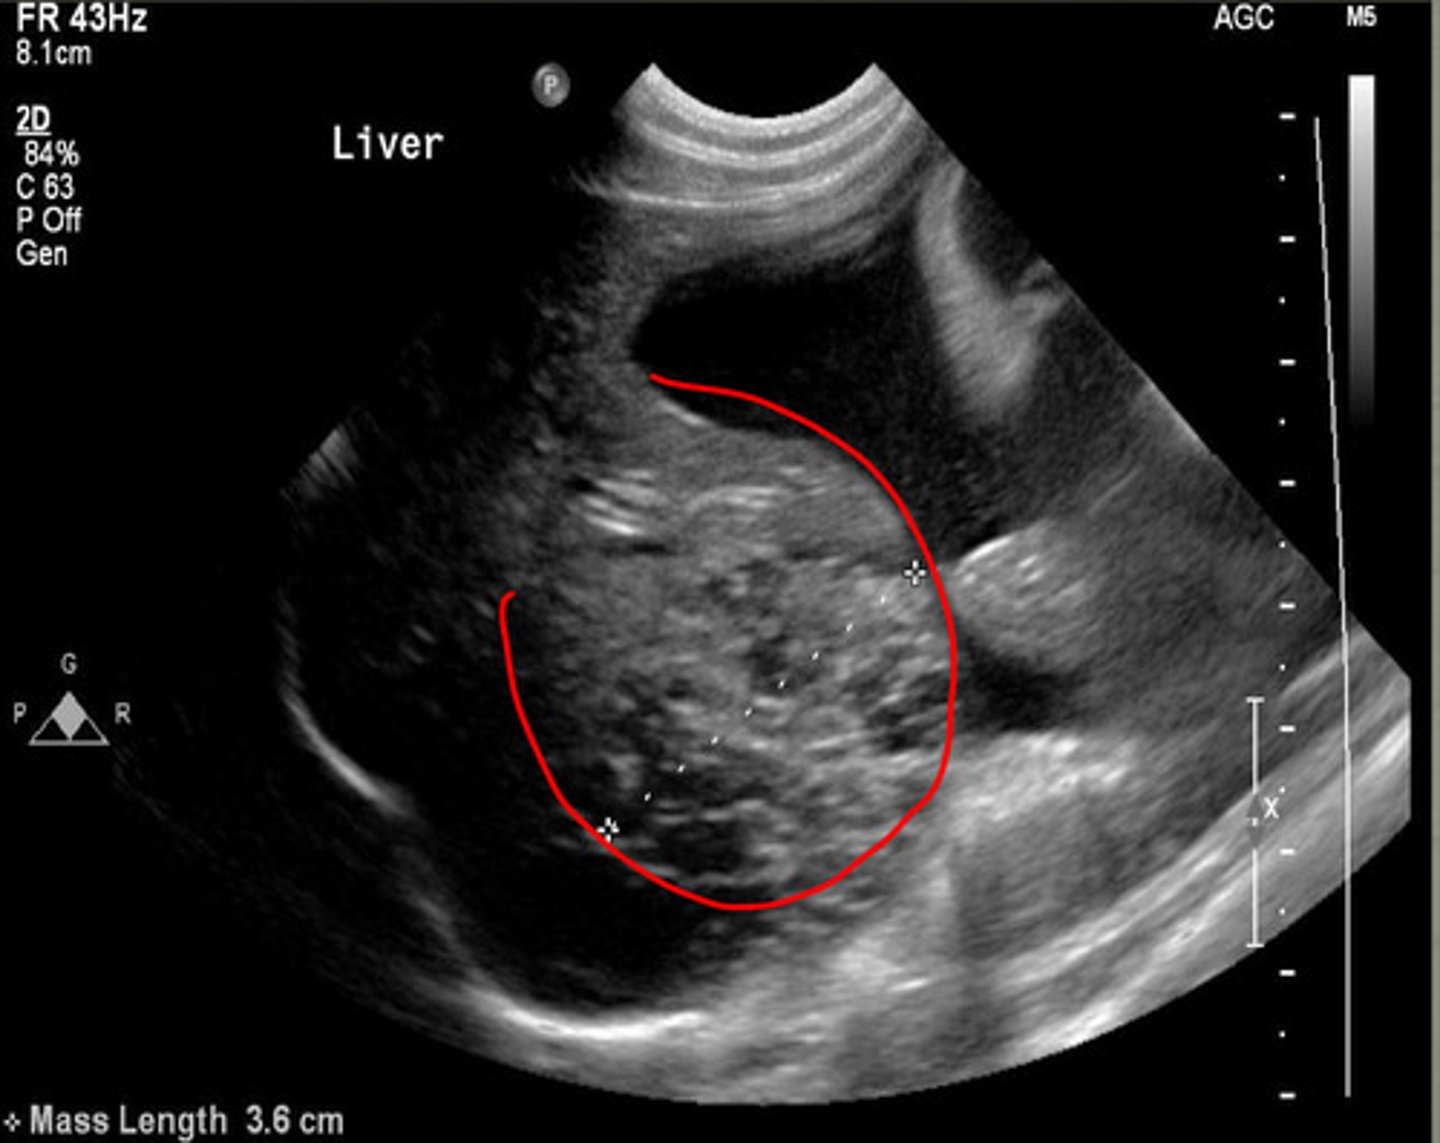

which US image shows the normal liver?

focal mass

what focal change does this show in the liver?

nodular lesions

what is the red arrow indicating from this ultrasound of the liver?

abnormal

is this a normal or abnormal liver US?